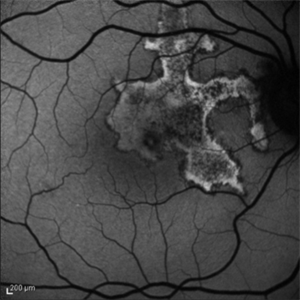

66 - year -old woman with acute visual acuity loss.

Photographer: Claudio Zett Lobo, UNIFESP

Condition/keywords: acute syphilitic posterior placoid chorioretinitis